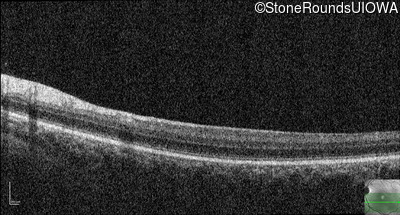

Optical Coherence Tomography - Right - 10/125 -1

Exemplar / OCT Stack

Optical Coherence Tomography - Left - 10/100 -1